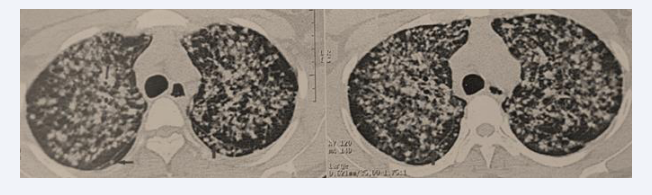

A chest CT scan revealed diffuse bilateral nodules and micronodules with a lymphatic distribution, involving all pulmonary regions and creating a miliary pattern. Some nodules were seen along the right and left fissures, forming a “beaded fissure” appearance (Figure 3).

Figure 3 Diffuse bilateral nodules and micronodules with lymphatic distribution, presenting a miliary pattern and perilymphatic fissure appearance.

Figure 3: Diffuse bilateral nodules and micronodules with lymphatic distribution, presenting a miliary pattern and perilymphatic fissure appearance.